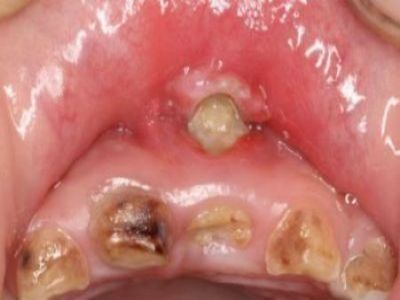

口腔

溃疡

创伤性溃疡磨牙旁边的肉被磨烂了图

创伤性溃疡发生在上牙膛靠近磨牙处的黏膜面,表面已经被磨烂,是因牙齿长期刺激所致,溃疡形态不规整,破溃的黏膜发白,继续刺激会扩大创面。